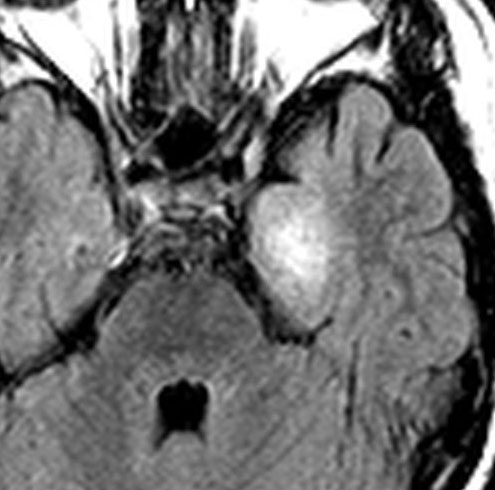

7才の時に音読でつかえるようになり,眼で何かを追っているような欠伸発作(左側頭葉てんかん)を繰り返すようになり,強直間代発作を生じて腫瘍が発見されました。下側頭回底面の皮質に発生した境界明瞭な腫瘍であり,周囲に脳浮腫を伴っています。T2強調画像で線維成分の多い硬い部分は低信号に,軟らかい部分はやや高信号となり,ガドリニウムでheterogenousに増強されます。グレード1の神経節膠腫としては非典型的な画像所見で術前診断は難しいもので,PXA pleomorphic xanthoastrocytoma も疑いました。もちろん治療としては開頭手術での全摘出です。術後に発作は消失しています。

構成要素はGFAP陽性の膠細胞が多く認められます。神経細胞様形態の細胞 ganglion cellではNeuN(+), CGA (+) synaptophisin (++), neurofilament (+)です。大型で腫大した核を有して核内封入体構造を有する好酸性もしくは淡明な細胞質を有する細胞が増殖してPXAを考えさせる部分像もありました。granular bodyも認められて,右の写真のように膠原線維の増生が目立つ部分もあります。これは表面の非常に硬い線維性の腫瘍部分です。MIB-1 indexは4%とやや高い値です。BRAF v600Eの変異が認められました。